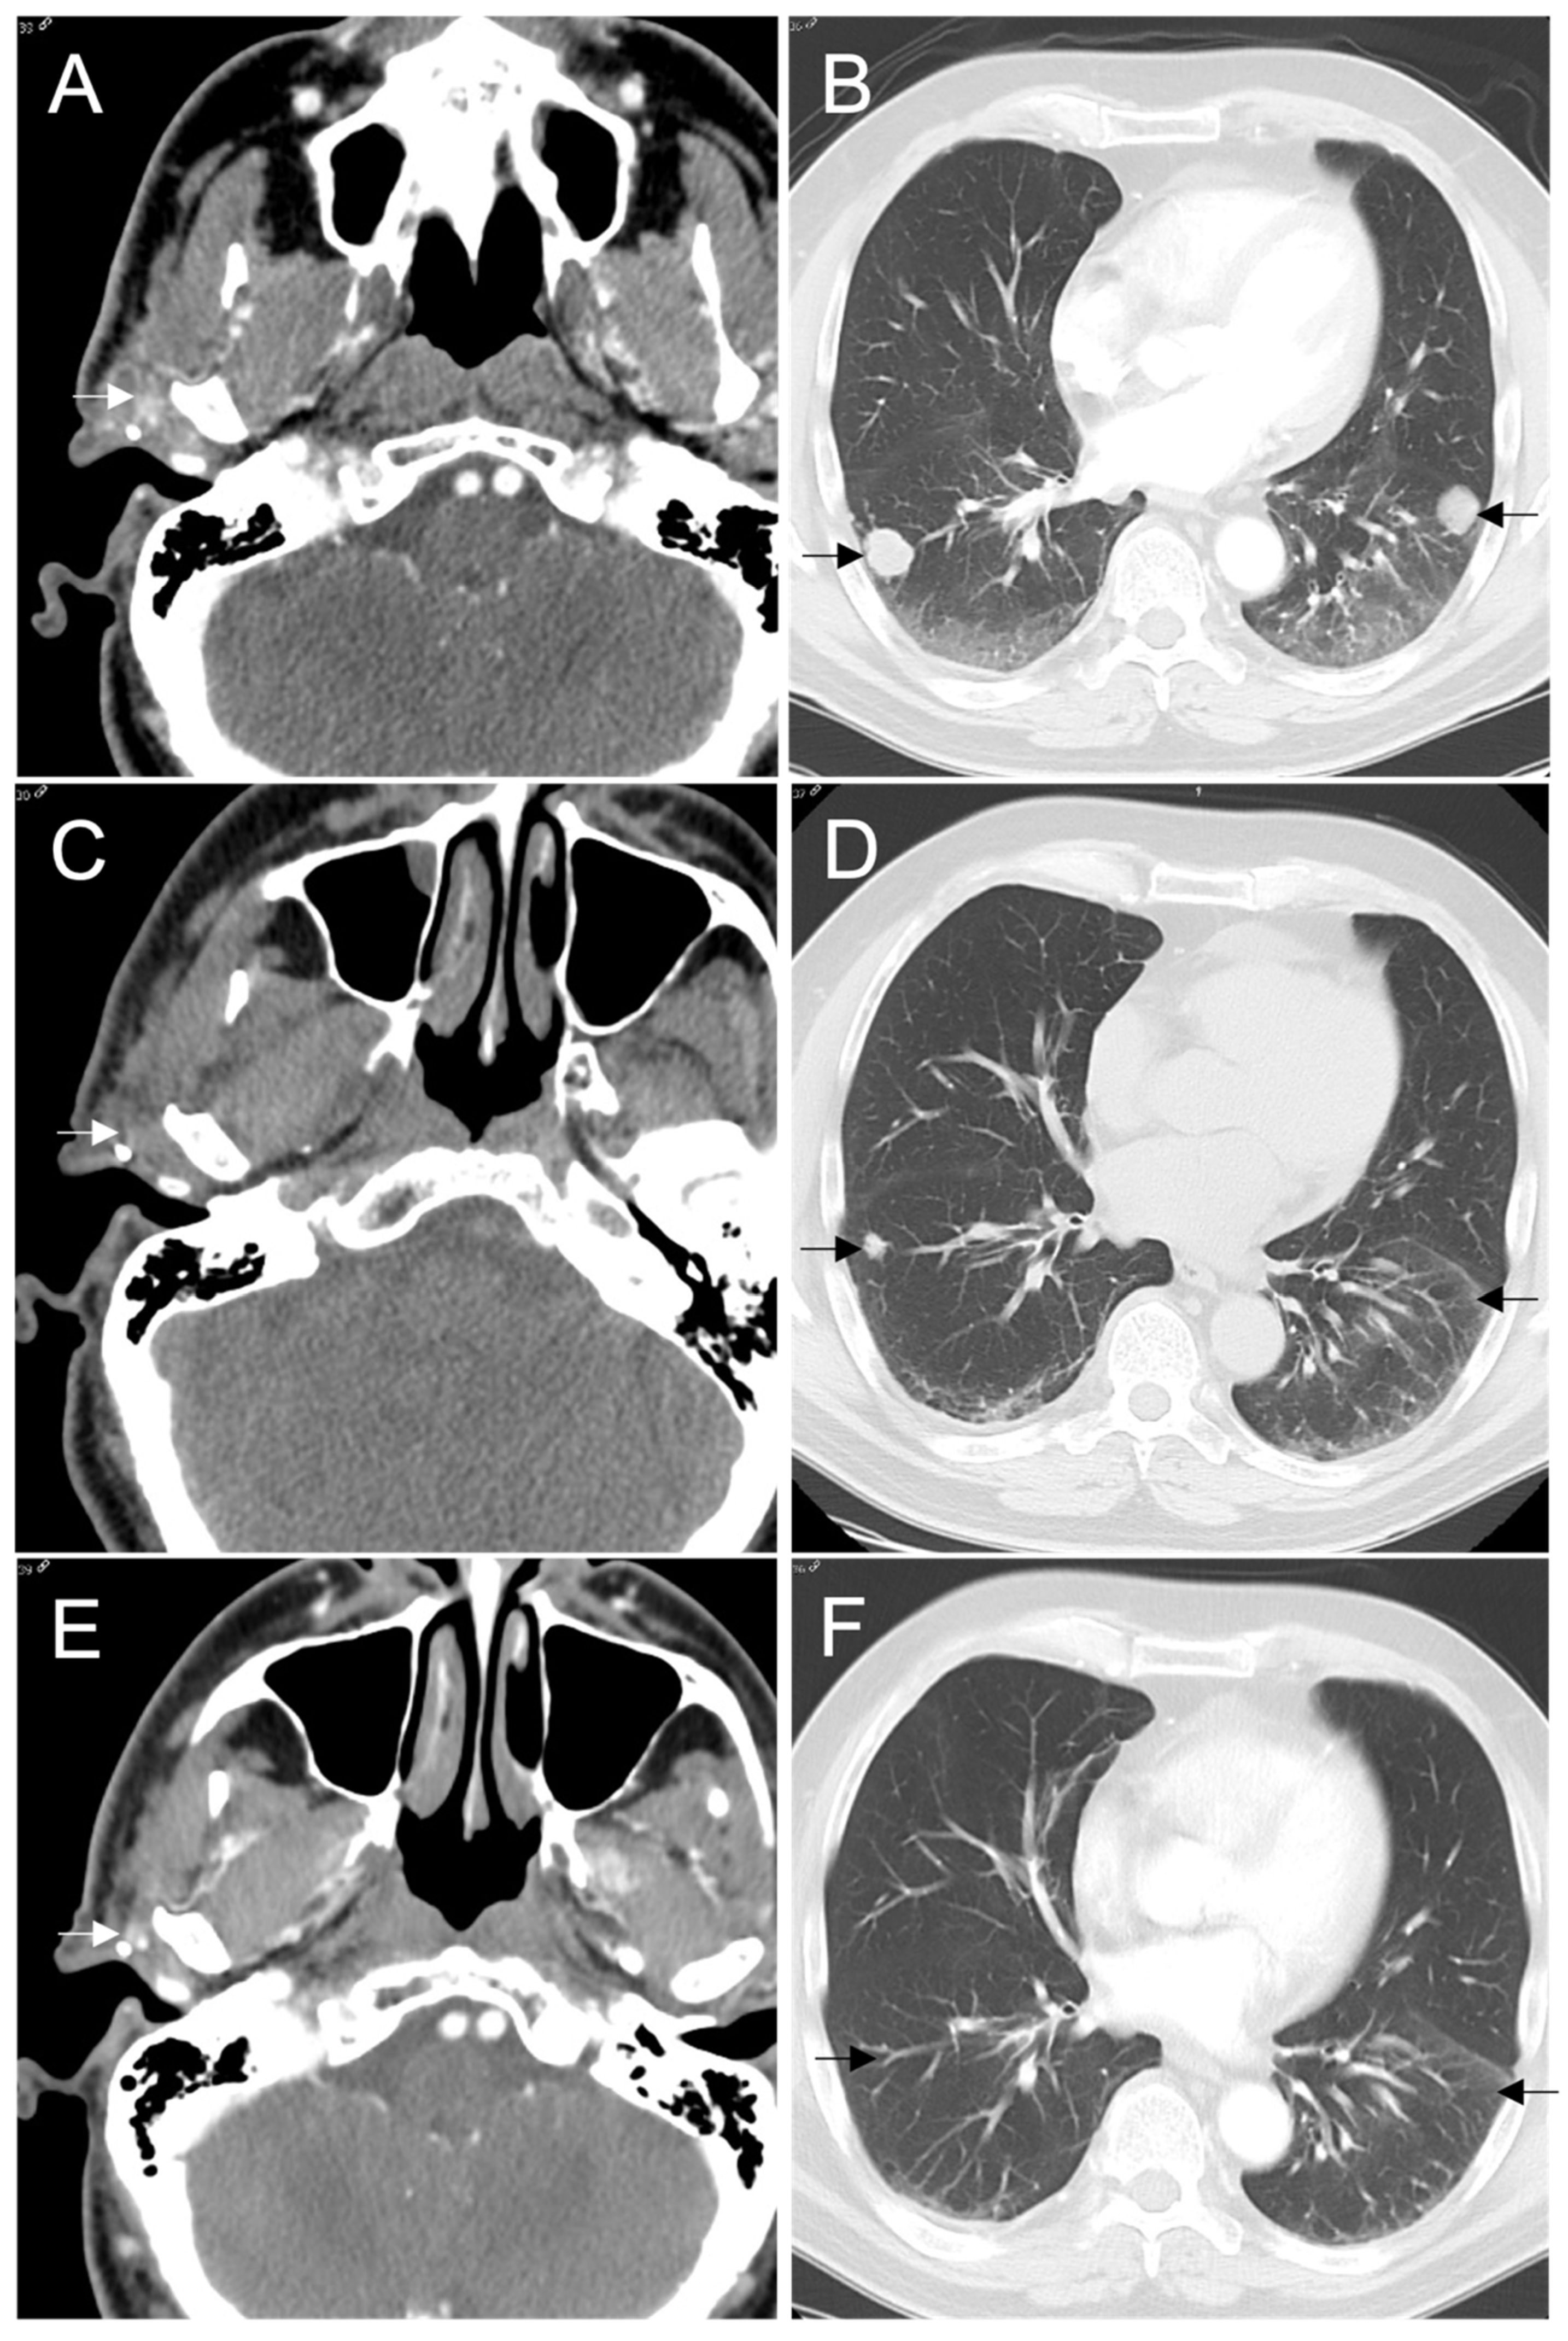

2. Case Presentation